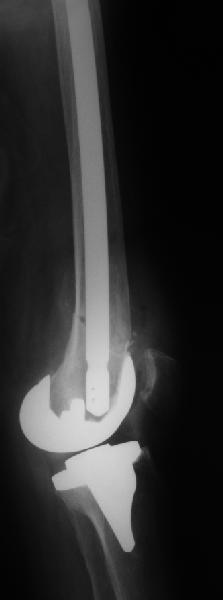

Поступила больная с перипротезным переломом

Перипротезный перелом у пациентки 67 лет . Эндопротезирование год назад . Сопутствующие нарушения ритма сердца и вес 120 кг при росте 185 .Думаю о мыщелковой пластинке с угловой стабильностью рыбинского исполнения остальное больной не потянуть . Заранее всем спасибо !

То, что планируется - наиболее распространенный подход. Еще менее инвазивный вариант - закрытый антеградный интрамедуллярный остесинтез. Мы используем гвозди, которые выпускаются предприятием ЦИТО, т.е. недорогие. Там в дистальное отверстие можно ввести 3 винта (2 снаружи и один навстречу), еще и угловая стабильность получается.

Уважаемый, Игорь! То что демонсрирует Александр Николаевич, высший пилотаж "neilinga" В нашей стране выполяется единичными спциалистами. Поэтому если не владеете методикой лучше пригласить к себе Челнокова. в случае накостного остеосинтеза, за который говорит ожирение и сопутствующая патология, не используте пластину Рыбинска. она не правильно предмоделирована и невесть из какого металла выполнена.поэтому неизвестно когда сломается при осевой нагрузке, и, кроме того,вы заведомо создадите вальгусную дефомацию, что повлечет за собой расшатывание компонентов. оптимальна в данном случае пластина "Synthes" скоминированными отверстиями. точно титан, идеально предмоделироана, винты надежно блокируются в отверстиях в отличие от Рыбинска.оперировать необходимо на спицевом дистракторе, спицы проводить перпендикулярно оси отломков. после репозиции под онтролем ЭОП чере два доступа пластину максимальной длины.дистальн заблокировать не менее 6 отверстий, проксимально-5.если нет возможности выполнить предложнные варианты, лучше пациентку перевести в отделение высшего уровня.Слишком высоки ставки. С уважением, Сергей.